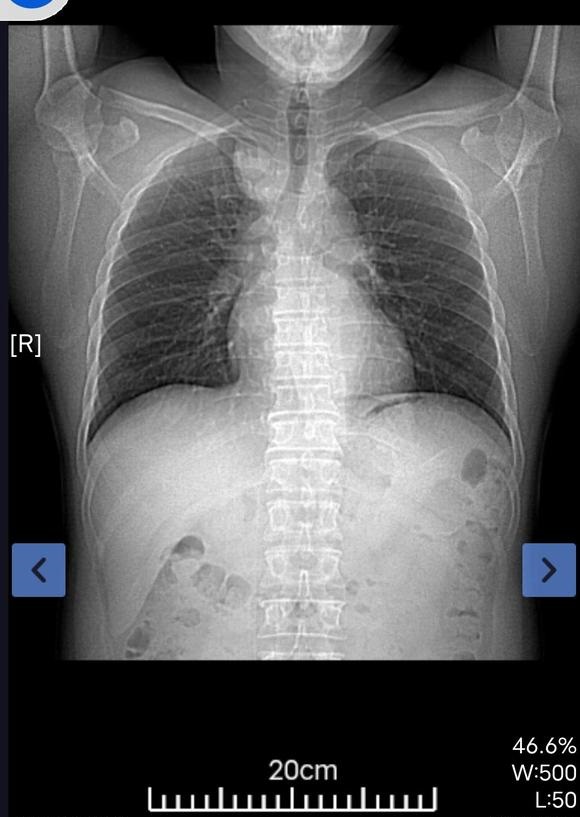

上周做了左肺下叶根治术局部淋巴清扫,下面是病理报告,我也看不懂,请问这个严重吗?淋巴结过两天才能出来结果,目前正在做基因...

共1张

请教各位帮我看看我母亲的病理报告